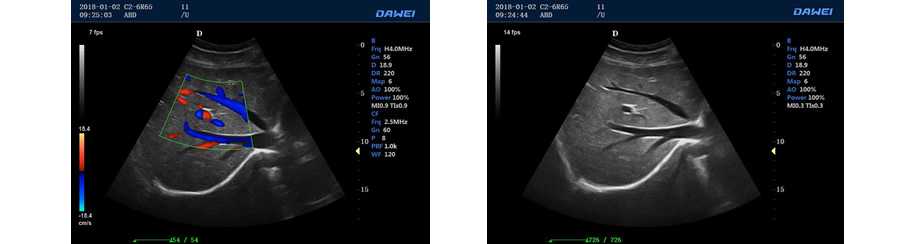

全數字彩色多普勒超聲診斷儀DW-PE522

DW-PF580

便攜式彩色多普勒

●全數字二維灰階成像單元

●彩色多普勒血流成像單元

●實時三維成像模式

設備用途:腹部、泌尿系統、子宮附件、胎兒、表淺結構/小器官、肌肉骨骼、心臟等